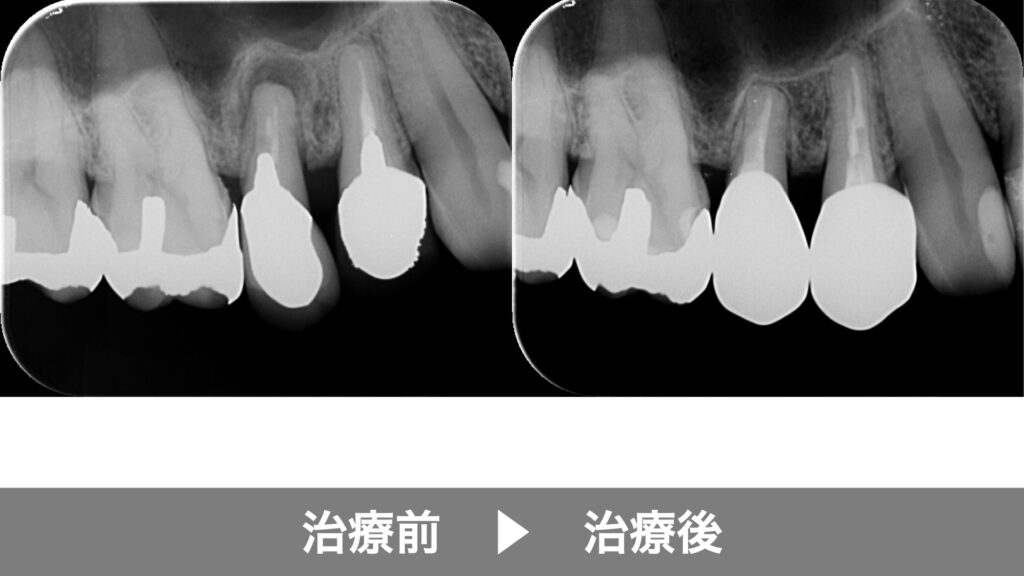

「以前、根の治療をしたのに痛みや腫れが治まらない」「レントゲンで根の先に影が残っている」といった場合、再根管治療が必要になることがあります。再治療では、過去の充填材料を除去し、見落とされていた根管を探す必要があるため、マイクロスコープが特に有効です。